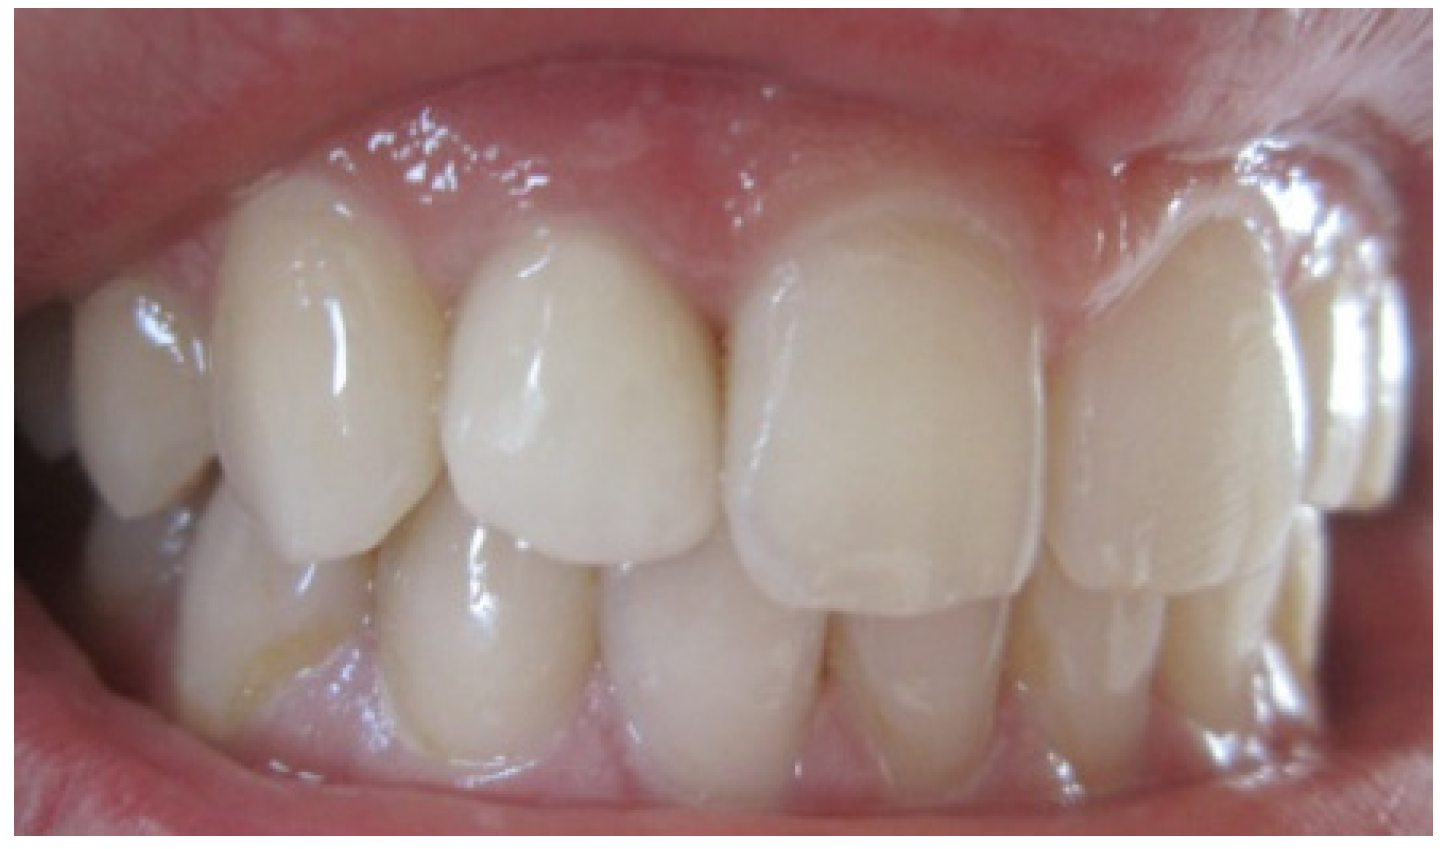

After 4 months of maturation, the abutment tooth was refined after placement and buildup of post and core materials (Figure 6). Later, a full arch impression was taken using a silicone material. An impression of the opposing dentition was also made with irreversible hydrocolloid. The shade was determined with the shade guide (VITA). The final restoration, Zirconia based crown, showing natural appearance with a correct gingival architecture was performed using the CAD/CAM technology. All of the team, including the prosthodontist, periodontist and the ceramist, were satisfied by the result—an aesthetic and functional restoration with a good marginal adaptation and an improved pink and white score (Figure 7). The most grateful of all was, however, our satisfied patient.

Figure 7. Final result showing an improvement of aesthetic appearance.